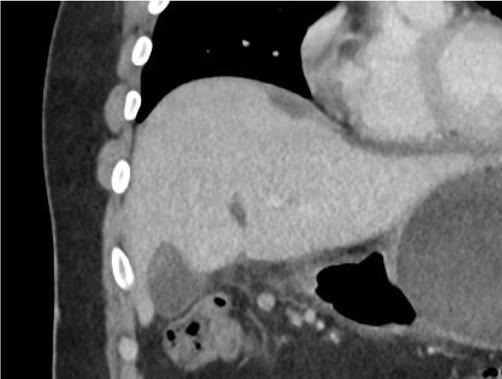

A31-year-oldobese,Hispanicmalepresentedtothe emergencydepartmentwithprogressivelyworseningleft upperquadrantabdominalpainfor fivedays.Thepainwas describedascramping,intermittent,andexacerbatedby bendingforward.Hedeniedpastmedicalhistory. Severaldayspriortopresentationthepatienthadbeen evaluatedbyhisprimarycarephysician.Hewasdiagnosed withmusculoskeletalpainandprescribedcyclobenzaprine. Sincetheevaluationbytheprimarycarephysician,thepain hadincreasedinfrequencyandintensity.Thepatientdenied anynausea,vomiting,fevers,diarrhea,orhematochezia.He did,however,reportintentionalweightlossof15kilograms. Tenweeksprior,thepatienthadingestedanIGB(Allurion,

formerlyknownasElipse),forweight-losspurposesunder thecareofaphysicianinJuárez,Mexico.

Oninitialevaluation,vitalsignswerenormalexceptfor sinustachycardiaat105beatsperminute.Hewasinmild distresswithmoderatetendernesstopalpationintheleftupper quadrant.Therewasnoguarding,rebound,orrigidity. Laboratoryevaluationshowedawhitebloodcellcountof 21.7 × 103 cellspercubicmillimeter(mm3)(referencerange 4.5 11 × 103 cells/mm3)withaneutrophilpredominanceof 18.9 × 103 cells/mm3 (2 7.8 × 103 cells/mm3)andanelevated bloodureanitrogenat25milligrams(mg)/deciliter(dL) (9–20mg/dL).Thepatient’selectrolytes,liverfunction tests,andserumcreatininewerewithinnormallimits. Acomputedtomography(CT)oftheabdomenandpelviswith intravenouscontrastwasorderedtoassessforbowel obstruction,perforation,andballoonintegrity.TheCT indicatedintraluminalgastricballoonwithanteriorgastricwall perforationwithoutevidenceofintestinalpathology(Image).

GeneralsurgerywasconsultedandobtainedaCT abdomenandpelviswithoralcontrast,whichdirectly showedextravasationintotheperitonealcavity.Thepatient wasemergentlytakentotheoperatingroomforan exploratorylaparotomy,abdominalwashout,removalofthe IGB,andgastricperforationrepair.Hewasstartedon piperacillin/tazobactamand fluconazoleforpurulent peritonitis.Afteranovernightstayinthesurgicalintensive careunit,hewastransferredtothesurgical floorwherehe remainedforthefollowing10days.Onday5,afollow-up uppergastrointestinalserieswithgastrografinwasobtained, andnocontrastextravasationwasnoted.Thepatient’sdiet wasadvanced,andhewasdischargedonpostoperativeday 10withamoxicillin-clavulanatefor10days.Forty-twodays afterdischargethepatientwasnotedtoberecoveringwellon afollowupvisit.